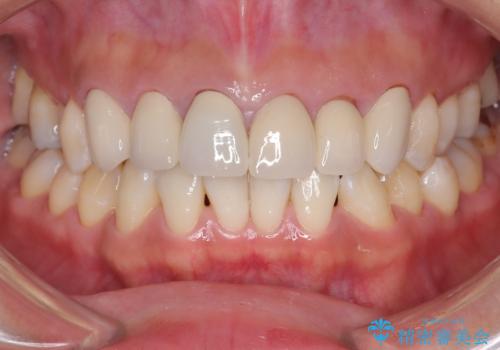

前歯のクラウンをやり変え、歯肉のラインも美しく

担当医 河口智英